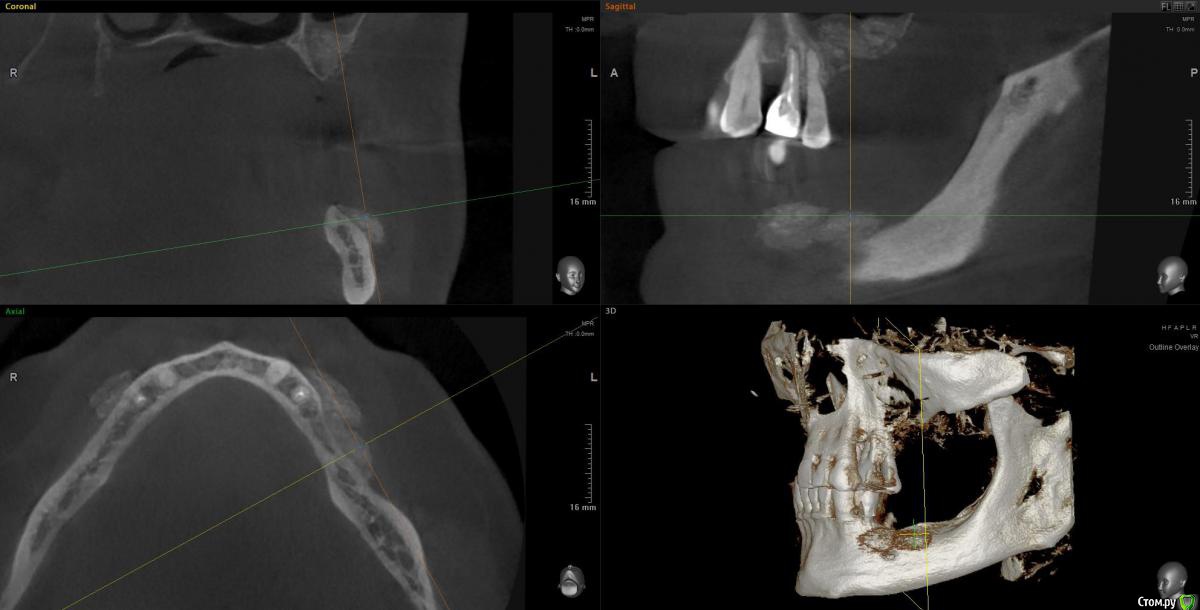

колесников Опубликовано 22 декабря, 2018 Автор Поделиться Опубликовано 22 декабря, 2018 Контроль просили. 1 пациент. Снимок майский,на тот момент 6-7 мес после вмешательства. Графтинг в обл имплантов и в промежутках ,3,4ый сектор 1 Ссылка на комментарий

колесников Опубликовано 16 февраля, 2019 Автор Поделиться Опубликовано 16 февраля, 2019 Спрашивали кт . Вид через 3-4 мес 1 Ссылка на комментарий

колесников Опубликовано 13 марта, 2019 Автор Поделиться Опубликовано 13 марта, 2019 Ну чтож, прошло 3 месяца,самое время посмотреть что там на кт. 1 Ссылка на комментарий